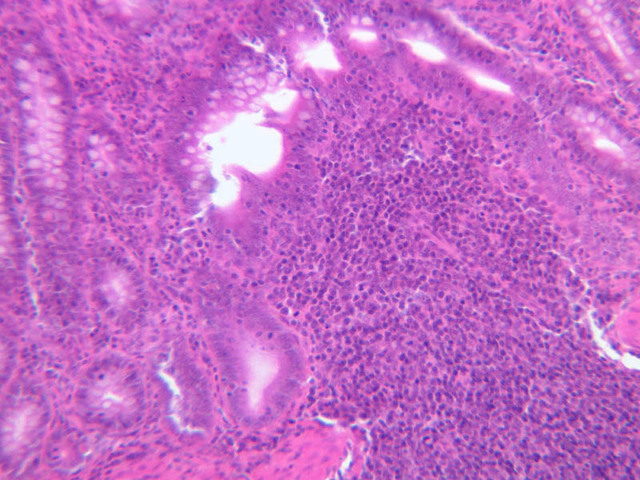

The visceral walls have concentrations of lymphoid tissues that comprise the body's filters against foreign organisms that attempt to enter by way of the alimentary, urinary, or respiratory tracts. The lamina propria is a layer of connective tissue underlying the epithelium of mucous membranes; lymphatic tissue is often found in the lamina propria. This lymphatic tissue can assume three forms; 1) diffuse lymphatic tissue, 2) solitary lymphatic nodules, and 3) aggregated lymphatic nodules. The simplest arrangement of lymphoid tissue occurs as diffuse patches of lymphocytes scattered in the lamina propria of the walls of visceral organs. When a patch becomes activated by antigens or foreign organisms, it takes on the appearance similar to a nodule in the cortex of a lymph node (see below). These nodules are not encapsulated and simply occur in the visceral wall as an accumulation of lymphocytes, macrophages, and plasma cells embedded in reticular tissue. Eosinophilic leukocytes are frequently seen.

Examine sections B-12 (jejunum, H&E [2.5x, 10x-labeled, 20x, 40x]); B-16, ileum, H&E [2.5x-labeled, 10x, 20x]; B-18, ileum, H&E [2.5x, 10x-labeled, 20x, 40x]; B-20, appendix, H&E [2.5x, 10x-labeled, 20x, 40x-labeled]) and find examples of diffuse lymphatic tissue. Solitary nodules of lymphoid tissue as well as diffuse lymphoid tissue can be found almost anywhere along the gastrointestinal system (this is sometimes called GALT, gut associated lymphoid tissue). The most noted areas with aggregated nodules are found in ileum—Peyer’s Patches (slide B-18, H&E [2.5x-labeled, 10x-labeled, 20x, 40x] [2.5x, 10x, 20x, 40x]), and appendix (slide B-20, H&E [2.5x, 10x, 20x, 40x] [2.5x, 10x,20x, 40x] [2.5x-labeled, 10x, 20x-labeled, 40x]). Peyer's Patch consists of aggregated nodules of lymphoid tissue. Compare the appearance of Peyer's patches to the lymphoid tissue in the appendix. In the appendix, the lymphoid tissue of the appendix appears as a continuous ring of lymphatic tissue in the lamina propria. What features differentiate the appendix from the Ileum?

In lymphatic nodules and nodes the term primary nodule refers to a nodule of homogeneously, tightly packed small lymphocytes. When lymphatic nodules have germinal centers they are called secondary nodules. A germinal center contains lighter staining, "B" lymphocyte precursors. Mitotic figures should be easily spotted in the core of the nodule. Compare these cells with the mass of small more differentiated lymphocytes that surround the germinal center. Some of these lymphocytes are cytokine producing T-Helper cells that are stimulating the proliferation of the lymphoblasts.